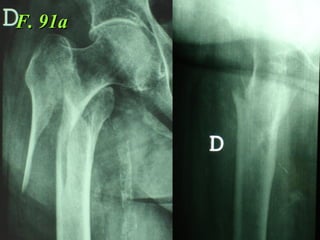

F. 91a

La placca a compressione percutanea (PC.C.P.) di Gotfried è un mezzo di sintesi studiato per assicurare un “impattamento controllato” delle fratture pertrocanteriche grazie alle due viti telescopiche prossimali che garantiscono una ottima stabilità rotazionale

Tradizionalmente si ritiene importante per la stabilità delle fratture pertrocanteriche l’integrità della parte mediale della metafisi prossimale del femore

In realtà la zona più importante per la ricostruzione di questo tipo di fratture è il muro laterale contro il quale si impatta il frammento metaepifisario mediale

Se il muro laterale è rotto o viene lesionato durante la sintesi , come spesso accade in fase di applicazione della vite cefalica dei chiodi endomidollari o della vite-placca, andremo incontro al collasso della frattura e ad un conseguente lungo periodo di impotenza funzionale

Con la placca di Gotfried non si è mai riscontrato un danno iatrogeno del muro laterale e nessun collasso della frattura.Ciò è dovuto al fatto che i fori per l’applicazione delle due viti prossimali sono di piccolo diametro (9 mm) rispetto ai 16-32 mm necessari per introdurre la vite cefalica di un chiodo endomidollare o di una vite-placca a compressione.